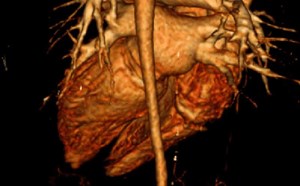

2nd Place Emage Winner: Cardiomyopathy